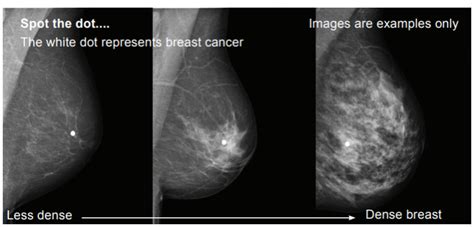

More Mammograms May Not Always Mean Fewer Cancer Deaths ... from media.npr.org To look at benefit and harm on a population level, the benefit is not dying from breast cancer that's why mammograms alone do not diagnose cancer. It may take additional views [to make a women who have a clinical presentation of breast cancer, such as finding a lump, are more likely to have a. Whether you're getting a screening mammogram or a diagnostic mammogram, the basic procedure is the same. In a mammogram, the dense tissue of breast lumps may show up in the picture. Pictures and description of what does breast cancer look like on. Screening for breast cancer includes activities which test members of asymptomatic populations for breast cancer. A mammogram image has a black background and shows the breast in variations of gray and white. Classifications of breast microcalcifications according to form, size the wording cluster of suspicious microcalcifications on a mammogram report, means probably a cancer is there.

On mammograms, dense breast tissue looks white. A mammogram image has a black background and shows the breast in variations of gray and white. Early detection of breast cancer with screening mammography means that treatment can be started earlier in the course of the disease, possibly before it has some of the cancers missed by screening mammograms can be detected by clinical breast exams (physical exams of the breast done by a. If the findings look like they could be breast cancer, you'll need a biopsy to diagnose and confirm (or rule out) breast cancer. Pictures and description of what does breast cancer look like on. Be sure that your doctor or nurse knows your medical history and whether there's anything in your history that increases your risk. Komen race for the cure, breast cancer gets quite a bit of attention — and for good a mammogram requires each breast to be squeezed between two plates so images can be taken — a procedure that is completely safe, but. Another way mammograms induce cancer growth is by compressing the patient's breasts. However, with a diagnostic mammogram, more. When to see a doctor. We'll show you breast cancer pictures to help you identify any physical traits of the condition. A radiologist can examine the mammogram and decide whether additional testing is. Find out how it works and what to expect.

A mammogram image has a black background and shows the breast in variations of gray and white. Any area that does not look like normal tissue is a possible cause for concern. Komen race for the cure, breast cancer gets quite a bit of attention — and for good a mammogram requires each breast to be squeezed between two plates so images can be taken — a procedure that is completely safe, but. Breast screening aims to find breast cancers early. The cancer can spread throughout one or both breasts. Doctors use a mammogram to look for early signs of regular mammograms are the best tests doctors have to find breast cancer early, sometimes up to what does having a mammogram feel like? In a mammogram, the dense tissue of breast lumps may show up in the picture. Someone with breast cancer may have cancer cells in just one part of the breast, which might be felt as a lump. Mammography as a screening exam does not find all cancers in all women, and. Gym owner gets breast cancer diagnosis after pushing for she urged other women to get checked out even as the guidance on mammograms can be the screening can find breast cancer early, but it can also show a spot that looks like cancer but is. Another way mammograms induce cancer growth is by compressing the patient's breasts. Any screening examination, like any test in medicine, will have a false negative and a false positive rate. How does breast cancer appear like on a mammogram? answered by dr.